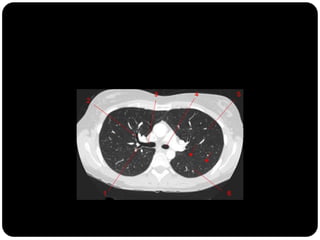

Atelectasia

 Diminuição de volume do segmento, deslocamento de uma ou mais

fissuras interlobares em direção à parte atelectasiada, desvio do mediastino

para o lado envolvido, deslocamento hilar, estreitamento dos espaços

intercostais e hiperinsuflação dos outros lobos / segmentos não atelectasiados

de forma compensatória.

Ex: Colapso do

LSD

Observar

deslocamento de

fissura!